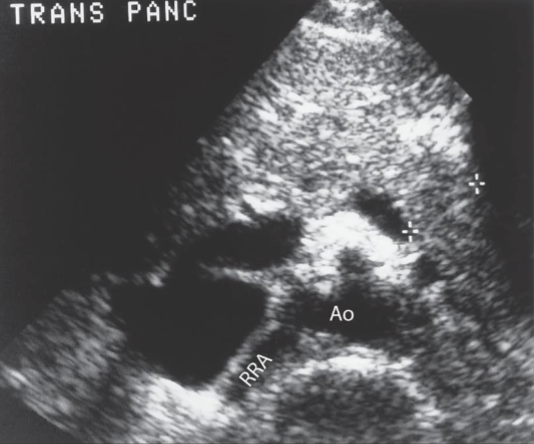

The "seagull sign" is obtained in what scan plane?

transverse

Where do the renal arteries branch from the lateral wall of the aorta?

inferior to the SMA

Which of the following vessels lies posterior and inferior to the pancreas?

superior mesenteric artery

Which one of the following vessels passes anterior to the uncinate process of the pancreas?